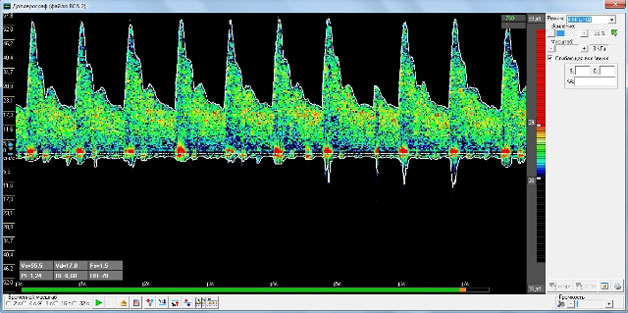

2. Допплерограмма внутренних сонных артерий, правой (сверху) и левой (снизу). Датчик 4 Мгц, постоянноволновой режим, многооконный режим ( 2 окна). Кровоток симметричен, показатели скорости кровотока, спектра, периферического сопротивления в пределах нормы.

5. Допплерограмма общих сонных артерий, правой (сверху) и левой (снизу). Датчик 4 Мгц, постоянноволновой режим, многооконный режим (2 окна). Кровоток симметричен, показатели скорости кровотока, спектра, периферического сопротивления в пределах нормы.

8. Многооконный режим (4 окна). Визуализирован кровоток в симметричных внутренних сонных артериях (слева) и позвоночных артериях (справа). Отмечается незначимая асимметрия линейной скорости кровотока (ЛСК) по позвоночным артериям - менее 20%. Вариант нормы.